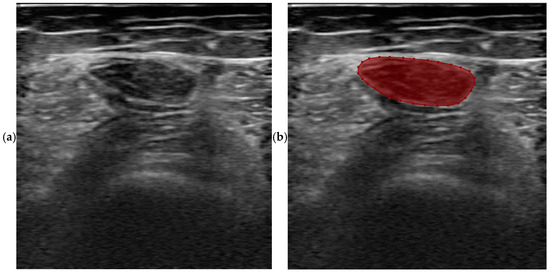

2.2. Database Annotation

2.3. Neural Networks of Deep Learning and Segmentations